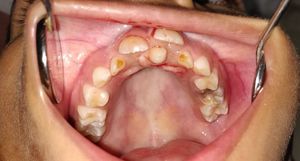

Supernumerary tooth

Mesiodens

Paedodontist